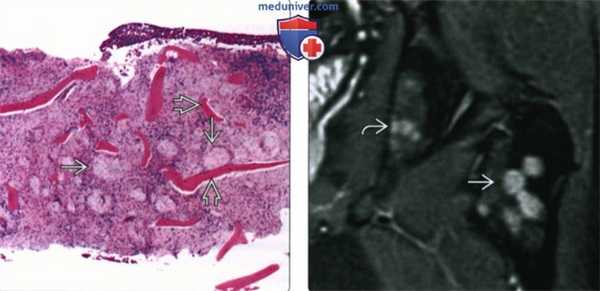

(Слева) Биоптат очага саркоидоза при малом увеличении: определяются неказеозные гранулемы, расположенные между трабекулами.

(Справа) МРТ проксимального отдела левой бедренной кости, PD-ВИ, режим подавления сигнала от жира, коронарный срез: у мужчины 45 лет с саркоидозом определяются образования в виде пушечных ядер в левой межвертельной области. Также обратите внимание на образования седалищной кости. После двух биопсий диагноз установить не удалось. Эти образования не визуализировались при рентгенографии и почти исчезли после шестимесячного наблюдения под контролем МРТ.